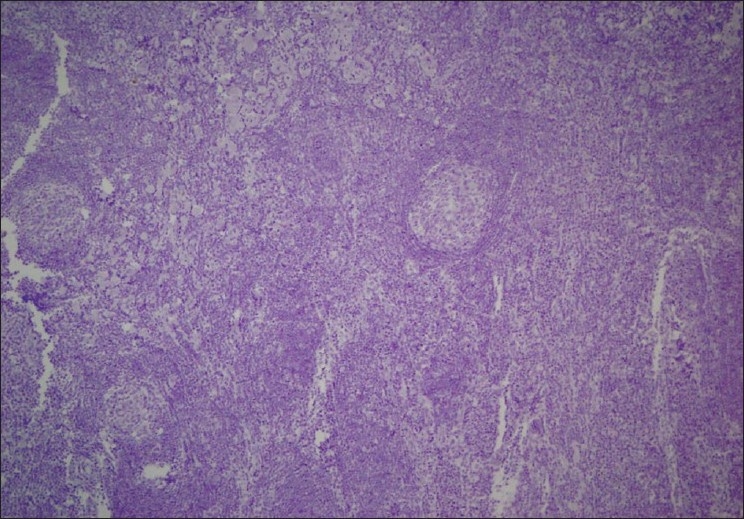

Case 3, a 27-year-old HIV-negative male, was diagnosed with nodular sclerosing HL in the thymus [Figure 3] and concurrently PCD in the mediastinal lymph nodes.

| Figure 3 Case 3. Nodular lesions with several Reed-Sternberg cells, H and E stain, ×40